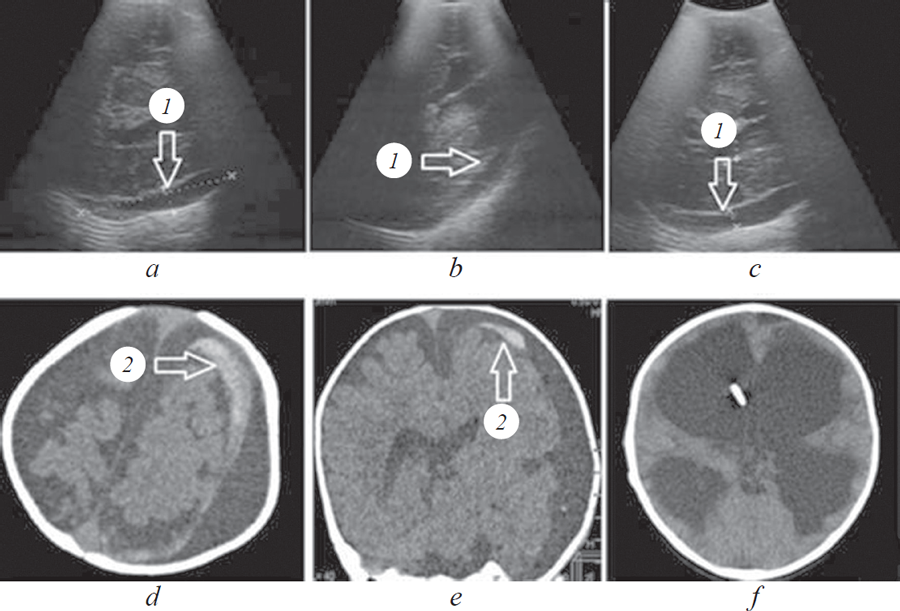

В качестве демонстрации приводим собственное наблюдение (рис. 1).

Рис. 1. Мальчик А.Р., 7 месяцев. Закрытая черепно-мозговая травма. Ушиб головного мозга средней степени тяжести. Суб арахноидальное кровоизлияние. Органическое поражение ЦНС. Сообщающаяся тривентрикулярная гидроцефалия. Субдуральные скопления в лобно-теменно-височных областях с двух сторон: a — УС-изображение в режиме S3,5 (доступ через височную кость, H2) через 8 часов после травмы; b — УС-изображение в режиме S3,5 (доступ через лобную кость); c — УС-изображение в режиме S3,5 (H2) через 72 часа после травмы; d, e — КТ головного мозга через 10 часов после травмы; f — КТ головного мозга через 16 дней. 1 — субдуральное скопление; 2 — участок кровоизлияния (указано стрелкой)

Мальчик А.Р., 7 месяцев. Получил травму головы в результате падения с высоты 50 см на деревянный пол. Ребенок госпитализирован в экстренном порядке и осмотрен через 8 часов с момента травмы. Родители предъявляли жалобы на вялость, многократную рвоту. Ребенок состоит на учете у невролога в связи с резидуально-органическим поражением ЦНС, задержкой моторного развития. Перинатальный анамнез отягощен: недоношенность 35 недель, асфиксия тяжелой степени, состояние при рождении — крайне тяжелое (оценка по шкале Апгар 5/6 баллов). Клинико-неврологическое состояние при поступлении расценено как средней степени тяжести (суммарная оценка по ШКГ — 14 баллов). При проведении неврологического осмотра диагностированы миоз, симметричное оживление сухожильных рефлексов с расширением рефлексогенных зон, повышение мышечного тонуса в нижних конечностях и наличие двусторонних патологических стопных знаков. При обзорной кранио графии данных за травматическое повреждение костей свода и основания черепа не получено. Оценку СВИ проводили с помощью ТУС из-за раннего закрытия родничков. В режимах S3,5 (H0), S3,5 (H1), S3,5 (H2) выявлено расширение желудочков головного мозга (Vt = 7 мм, VLD = 23 мм, VLD = 24 мм) и гипер эхогенный объект «серповидной формы» с акустической тенью без масс-эффекта. По результатам клинико-сонографической оценки определены показания для проведения КТ головного мозга, при которой верифицирована атрофическая гидроцефалия и массивное кровоизлияние в субдуральное пространство. В течение последующих 72 часов наблюдали ухудшение состояния — угнетение сознания до 13 баллов по ШКГ, повторную рвоту. По результатам динамических клинико-сонографических осмотров диагностировано прогрессирование размеров внутричерепного кровоизлияния и признаков отека головного мозга. В дальнейшем, через 16 дней, по данным динамической клинико-сонографической оценки, отмечены стабилизация неврологического состояния и частичный регресс внутричерепной гематомы.